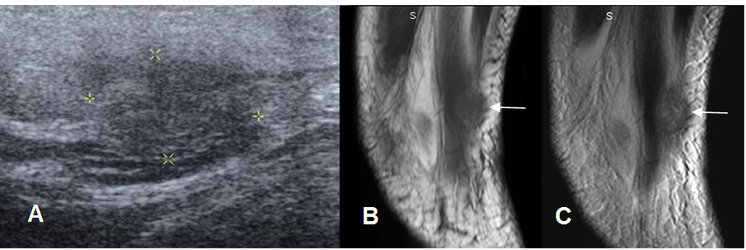

Fig 14 B. Hematoma muscular organizado.

A: Ecografía: Imagen ovalada, hipoecoica y mal definida.

B: RM sagital en T1 y C: RM sagital en T2. La lesión es hipointensa en ambas secuencias y aparición en el lugar de un trauma previo, correspondiendo a fibrosis.